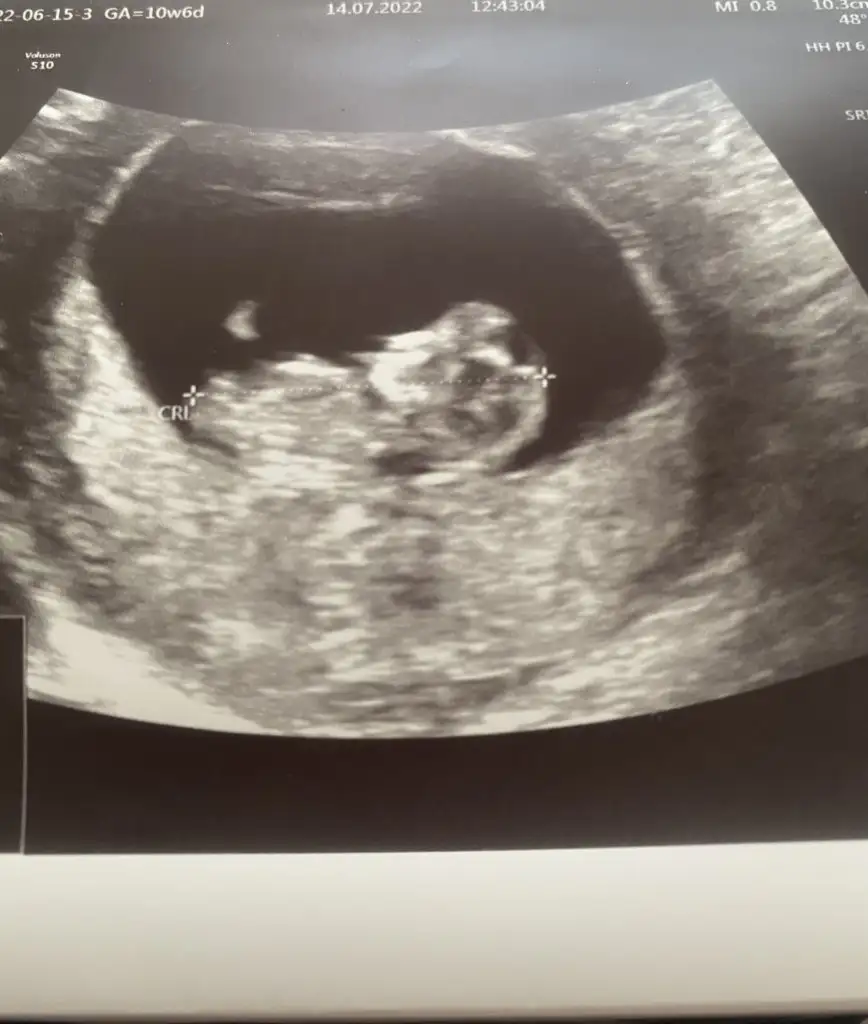

Canım banada yorum yapar mısınız 10 haftalık karından

Eklentiler

• 10. hafta.webp

10. hafta.webp

23,7 KB · Görüntüleme: 63